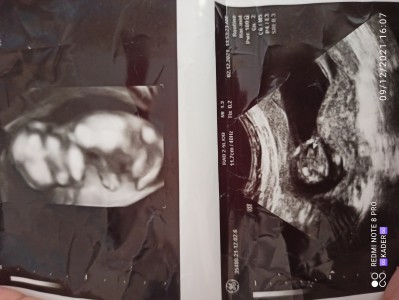

4 Aylık oluk ama hâlâ cinsiyet tahmini yapılmadı

Gebelik haftası 14+6

4 aylık değilsiniz henüz daha 3 aylık gebesiniz cinsiyet için de erken zaten . Kız doğdu içime.